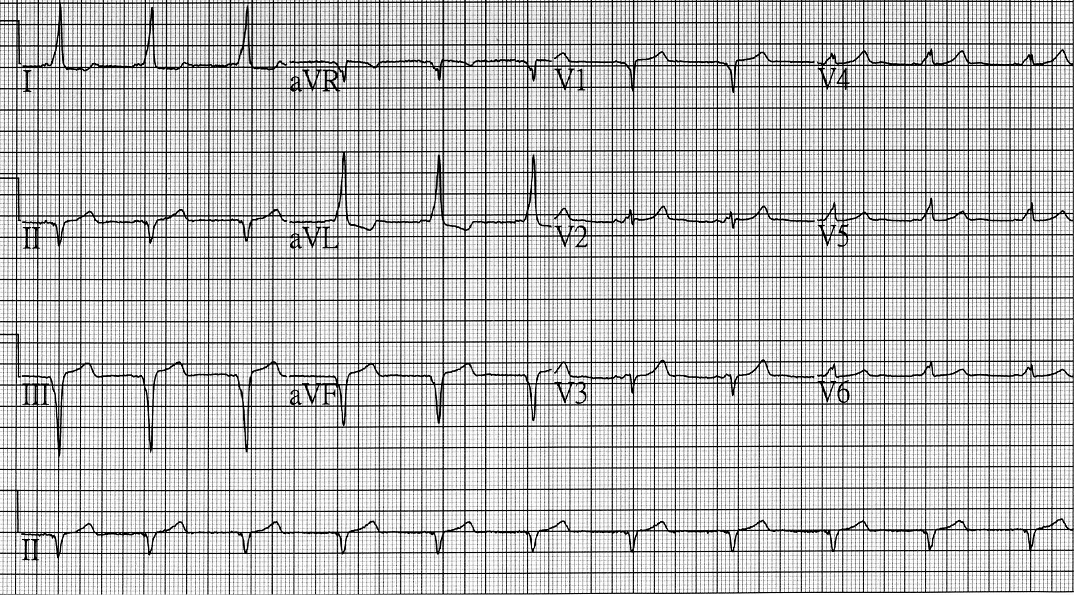

【107-2 醫學(三) 第16題】一位44歲女性因心悸至門診檢查,心電圖顯示如下圖,其附屬路徑或旁道(accessory pathway)最可能位在何處?

詳解

破題關鍵

這張心電圖顯示典型的沃爾夫-帕金森-懷特症候群(WPW syndrome)特徵,解題核心在於判讀各導程的Delta波方向,以定位附屬路徑(accessory pathway)的位置。